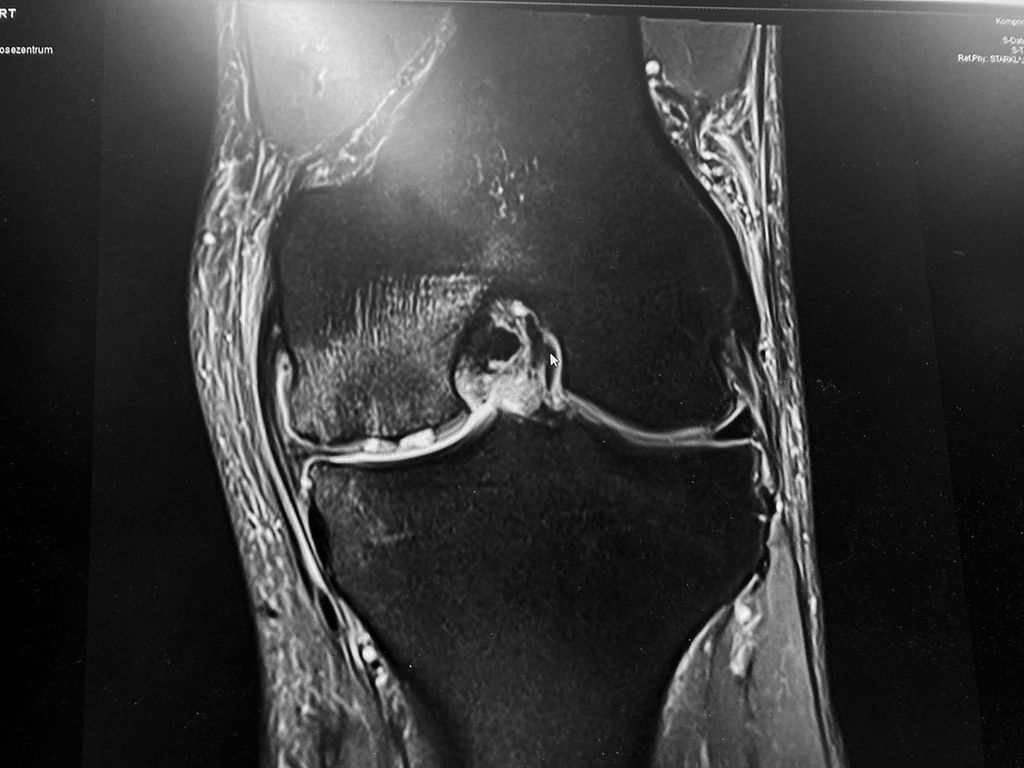

Eine der am häufigsten beobachteten Veränderungen des subchondralen Knochens sind die subchondralen Knochenmarksläsionen (BML), auch bekannt als subchondrales Knochenödem, definiert als eine Veränderung der MRT-Signalintensität des Knochenmarks, die auf T1- und T2-gewichteten Bildern zu sehen ist und am besten mit Fettsuppressions-STIR-Sequenzen dargestellt wird. Das Vorhandensein von subchondralem BML weist im Allgemeinen auf eine Form der Verletzung hin, die das Ergebnis eines akuten Traumas, von Stoffwechselanomalien, einer vorübergehenden Überbelastung infolge einer Gelenkknorpelverletzung oder einer chronischen Überbelastung wie bei OA sein kann. Diese Verletzungen führen zu einem Ungleichgewicht zwischen den Reizen und der Fähigkeit des Knochens, sich zu remodellieren und den physiologischen und funktionellen Zustand wiederherzustellen. In der MRT wird dies durch Veränderungen der Knochensignalintensität dargestellt. Das Muster dieser Veränderungen kann je nach Ätiologie der subchondralen BML unterschiedlich sein, was sich auch auf die Prognose und die mögliche Behandlung auswirkt. Die subchondrale BML, die sekundär zu Gelenkknorpeldefekten auftritt, weist im Allgemeinen auf eine Beeinträchtigung der Gesundheit des subchondralen Knochens hin und kann entweder einen reversiblen oder einen irreversiblen Prozess darstellen. Ein Beispiel für einen reversiblen Zustand ist der typische „bone bruise“, der nach einer ACL-Ruptur festgestellt wird, während die BML, die bei OA-Knien auftritt, zu einer Insuffizienzfraktur oder sogar zu einer Osteonekrose führen kann, was einen irreversiblen Prozess darstellt. Diese Osteonekrose kann dann im Kollaps des subchondralen Knochens enden, was im Verlauf des Morbus Ahlbäck das Endstadium darstellt.

Abb. 2: Knochenmarködem mit subchondraler Insuffizienzinfrakturierung (SCIF) bei Knorpelschaden und Meniskusverlust bei einer 60-jährigen Patientin mit plötzlicher Zunahme der Belastungsschmerzen. Therapie ist hier mit Entlastung und Bisphosponaten iv angezeigt.